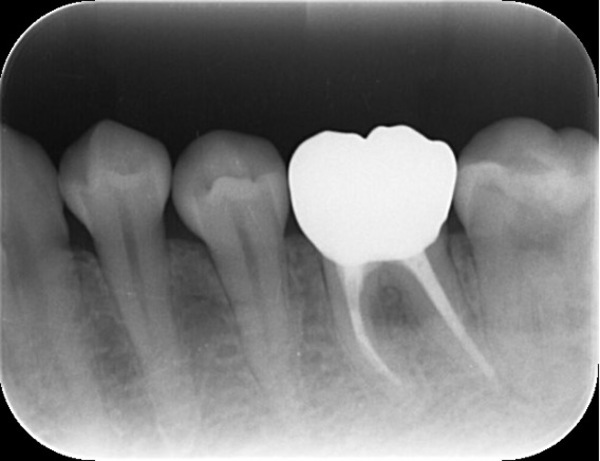

こちらが根管治療終了後から1年3ヶ月後のX線写真です。

完全に骨が回復したと言って良い状況となりました。